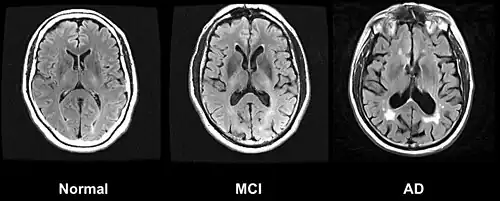

Normal: Vergleichsbild ohne Alzheimer-typische Veränderungen.

MCI: Mild cognitive impairment, Frühphase der Erkrankung mit nur leichten Einschränkungen. Als Zeichen der Schrumpfung des Gehirns sind die dunklen, flüssigkeitsgefüllten Räume außer- und innerhalb des Gehirns und die Abstände zwischen den Windungen vergrößert.

AD: Alzheimer-Krankheit mit deutlicher Schrumpfung des Gehirns.